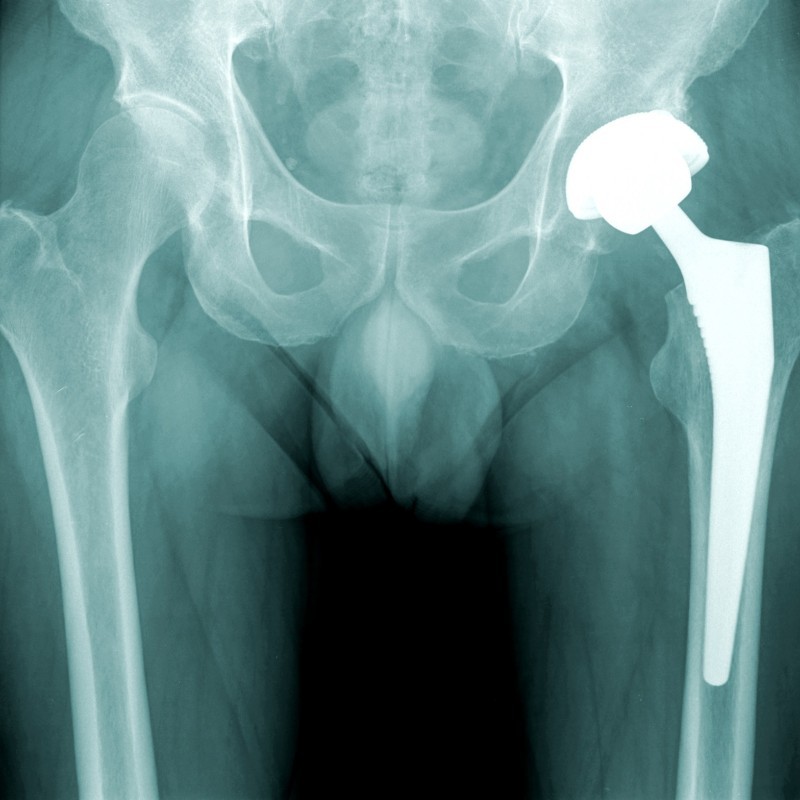

Waarom een Totale Heupprothese?

Wanneer u bij toenemende slijtage (artrose) van het gewrichtskraakbeen ook meer pijnklachten ervaart, kan het plaatsen van een prothese (kunstgewricht) een oplossing zijn. Bij de chirurgische ingreep wordt het beschadigde heupgewricht vervangen door een kunstgewricht. Zowel de heupkom als de heupkop kunnen dan vervangen worden. Dit wordt vaak gedaan bij mensen die lijden aan ernstige artritis, heupfracturen of andere aandoeningen die pijn en bewegingsbeperkingen veroorzaken in de heup.

Het doel van een totale heupprothese is om pijn te verminderen en de functie te verbeteren. Dit stelt de patiënt in staat om dagelijkse activiteiten met minder moeite en discomfort uit te voeren. Uiteindelijk kan dit leiden tot een verbeterde kwaliteit van leven. Fysiotherapie Heikant werkt hierbij samen met meerdere ziekenhuizen en klinieken.